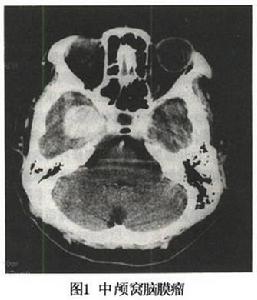

5.CT和MRI掃描 可確定腫瘤的部位和大小,絕大多數可作出定性診斷。CT掃描示邊界清晰的均勻高密度影,增強後顯著。少數呈混合密度或低密度改變。MRI見腫瘤多數呈等信號,增強後明顯強化。

2.CT和MRI 中顱窩腦膜瘤在CT的表現為邊界清楚的較高密度影像注藥對比後明顯增強少部分病人表現為混雜密度區如腫瘤有鈣化,CT顯著為極高密度(圖1)。MRI均可見長T1短T2信號腫瘤邊界清楚。